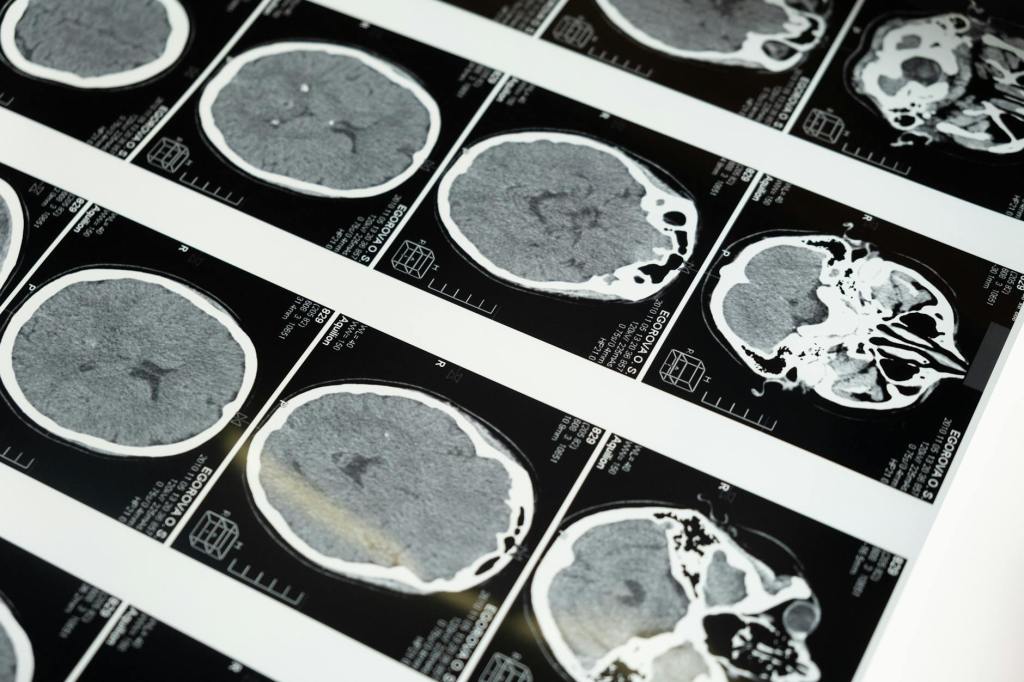

A quick Google search led me to diagnose myself with MS, so I called my primary care doctor. She ordered a brain MRI and five vials’ worth of blood tests. Fortunately, the MRI showed that I didn’t have any sign of MS. I did have a small white spot in the frontal lobe, something that falls into the “as we get older” category of benign ailments, and a blocked sinus cavity. Otherwise, I got a clean bill of brain health.

Six months later, a day or two after my follow-up MRI, I got an email saying the results of my test were available. My follow-up appointment with the neurologist was not for another few days, and naturally I was curious, so I went to the hospital’s portal and opened the report. The good news, the radiologist reported, was that nothing had changed in my brain. The small flare in the frontal lobe was exactly the same size. The blocked sinus was still blocked. And the meningioma had not grown significantly since the last scan.

Apparently, the first radiologist completely missed the small tumor lurking quietly in the center of my head. The second radiologist saw the tumor and compared measurements with the images from six months before. He was happy to report no changes.

I immediately Googled and spent an hour or two immersed in the dark world of brain tumors. While usually referred to as brain tumors, meningiomas live on the lining of the brain cavity, not on the brain itself. They cause damage by growing large and pressing on things like nerves and blood vessels. I learned that most people find out they have a meningioma in one of two ways: either they start to have symptoms like headaches, seizures, or vision loss, or it’s picked up in an MRI that was looking for something else, like mine. I was definitely lucky it was caught early, before it started doing any damage. I also learned that meningiomas grow slowly and are nearly always benign. Good news, indeed.